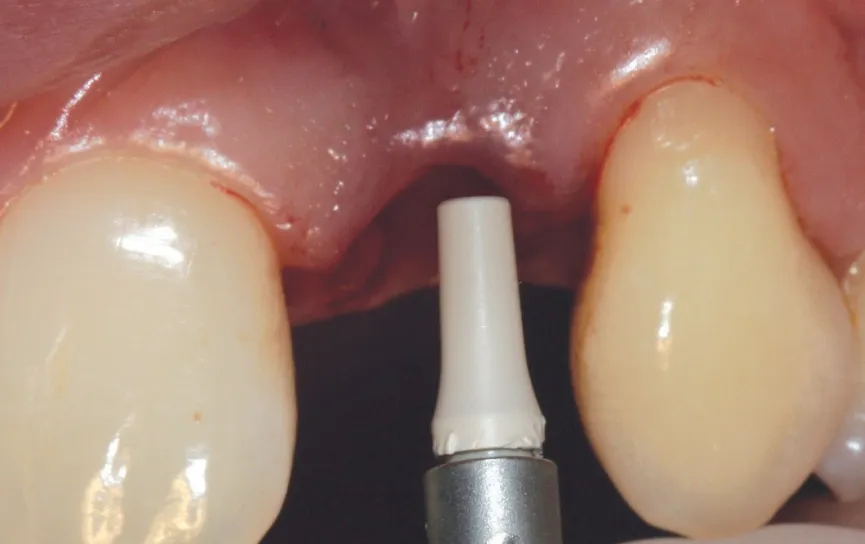

图 31 :印模转移杆就位。

图 32 :使用聚醚印模材料 (Impregum®) 取模。

图 33 :最终完成,自然微笑。

图 34 :挤压安装最终修复体。